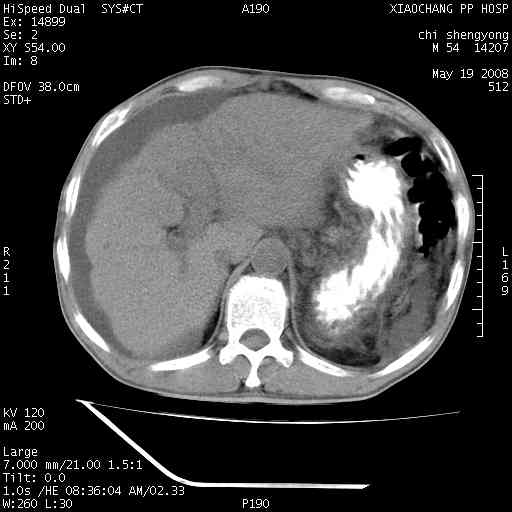

以下是引用zjzjr在2008-5-21 10:52:00的发言:[br]肝左叶巨块型肝癌伴门静脉左支瘤栓形成.肝硬化、腹水,胃底静脉曲张,脾术后改变。

以下是引用随光逐影在2008-5-21 16:20:00的发言:[br]1)肝左叶肝癌伴门静脉左支瘤栓形成,腹膜后淋巴结转移。2)肝硬化、腹水、胃底静脉曲张。3)胆囊炎。4)脾脏缺如,为切除术后所致。